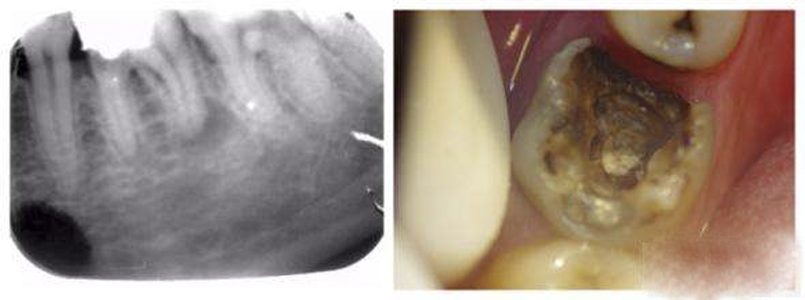

牙髓炎圖片

牙髓炎